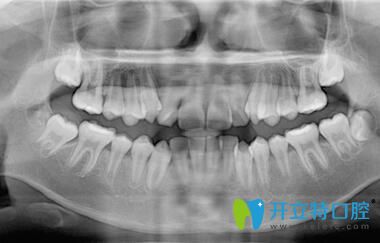

深圳正夫口腔的正畸醫(yī)生面診后,說我的牙齒屬于牙列不齊、前牙擁擠;針對我的情況,又拍了牙片;然后才制定矯正方案,建議戴傳統(tǒng)金屬托槽或球面自鎖托槽,也把這兩種牙套的優(yōu)缺點和價格都做了詳細(xì)的介紹。

我在深圳正夫口腔做牙齒矯正前拍片